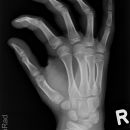

Fraktur MC5

subcapitale MC 5 Fraktur